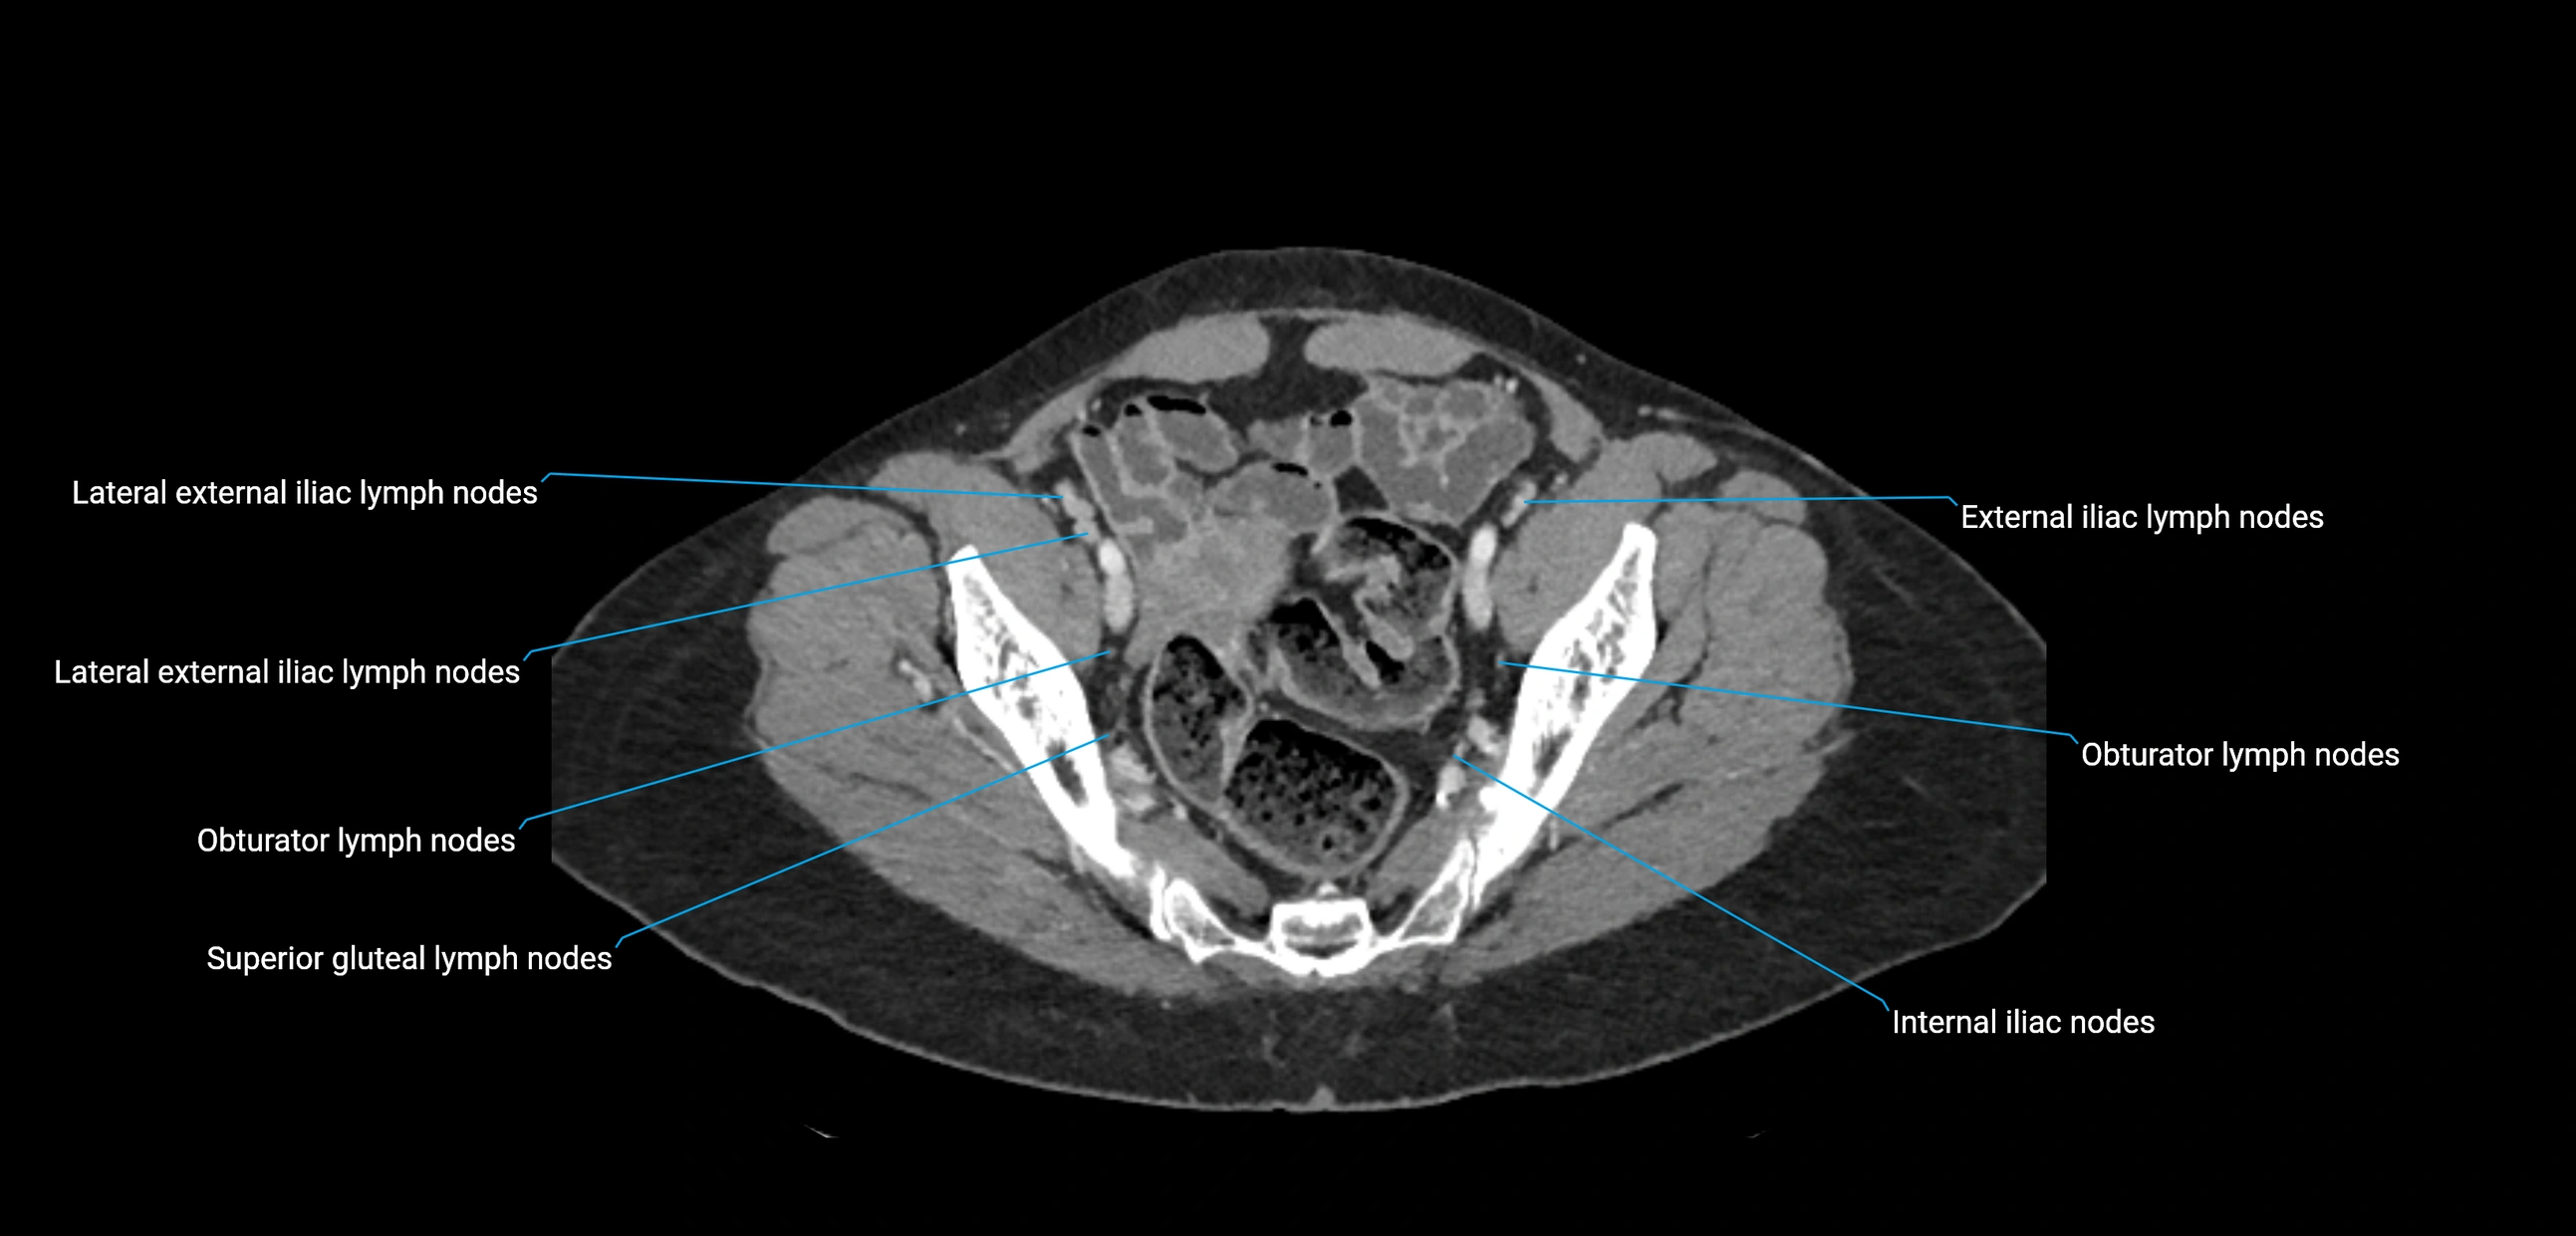

CT image

image